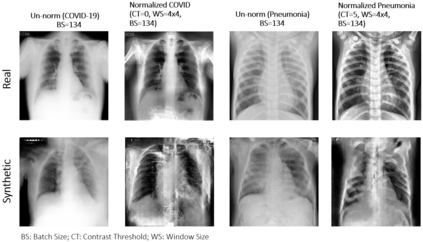

Biomedical image datasets can be imbalanced due to the rarity of targeted diseases. Generative Adversarial Networks play a key role in addressing this imbalance by enabling the generation of synthetic images to augment datasets. It is important to generate synthetic images that incorporate a diverse range of features to accurately represent the distribution of features present in the training imagery. Furthermore, the absence of diverse features in synthetic images can degrade the performance of machine learning classifiers. The mode collapse problem impacts Generative Adversarial Networks' capacity to generate diversified images. Mode collapse comes in two varieties: intra-class and inter-class. In this paper, both varieties of the mode collapse problem are investigated, and their subsequent impact on the diversity of synthetic X-ray images is evaluated. This work contributes an empirical demonstration of the benefits of integrating the adaptive input-image normalization with the Deep Convolutional GAN and Auxiliary Classifier GAN to alleviate the mode collapse problems. Synthetically generated images are utilized for data augmentation and training a Vision Transformer model. The classification performance of the model is evaluated using accuracy, recall, and precision scores. Results demonstrate that the DCGAN and the ACGAN with adaptive input-image normalization outperform the DCGAN and ACGAN with un-normalized X-ray images as evidenced by the superior diversity scores and classification scores.